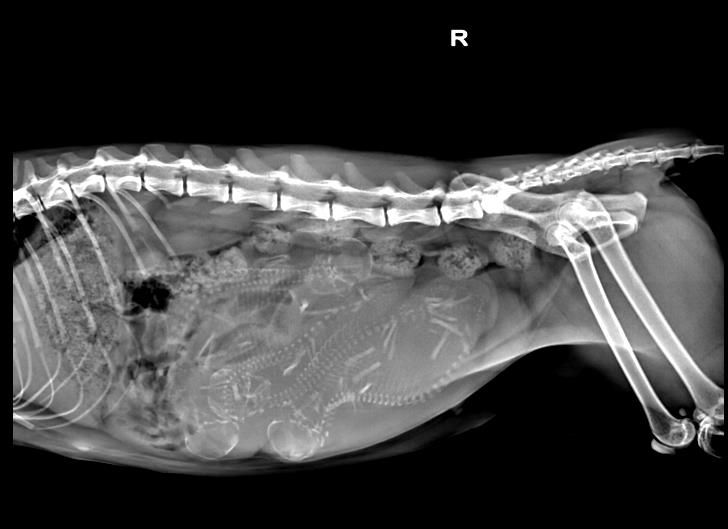

X线拍片检查:可判断胎儿体格大小、胎儿数量及胎位。在有些情况下,如果子宫内有气体或者胎儿颅骨塌陷或者其他骨头的位置出现异常,则说明发生了胎儿死亡。也可判断产道的大小与形状。